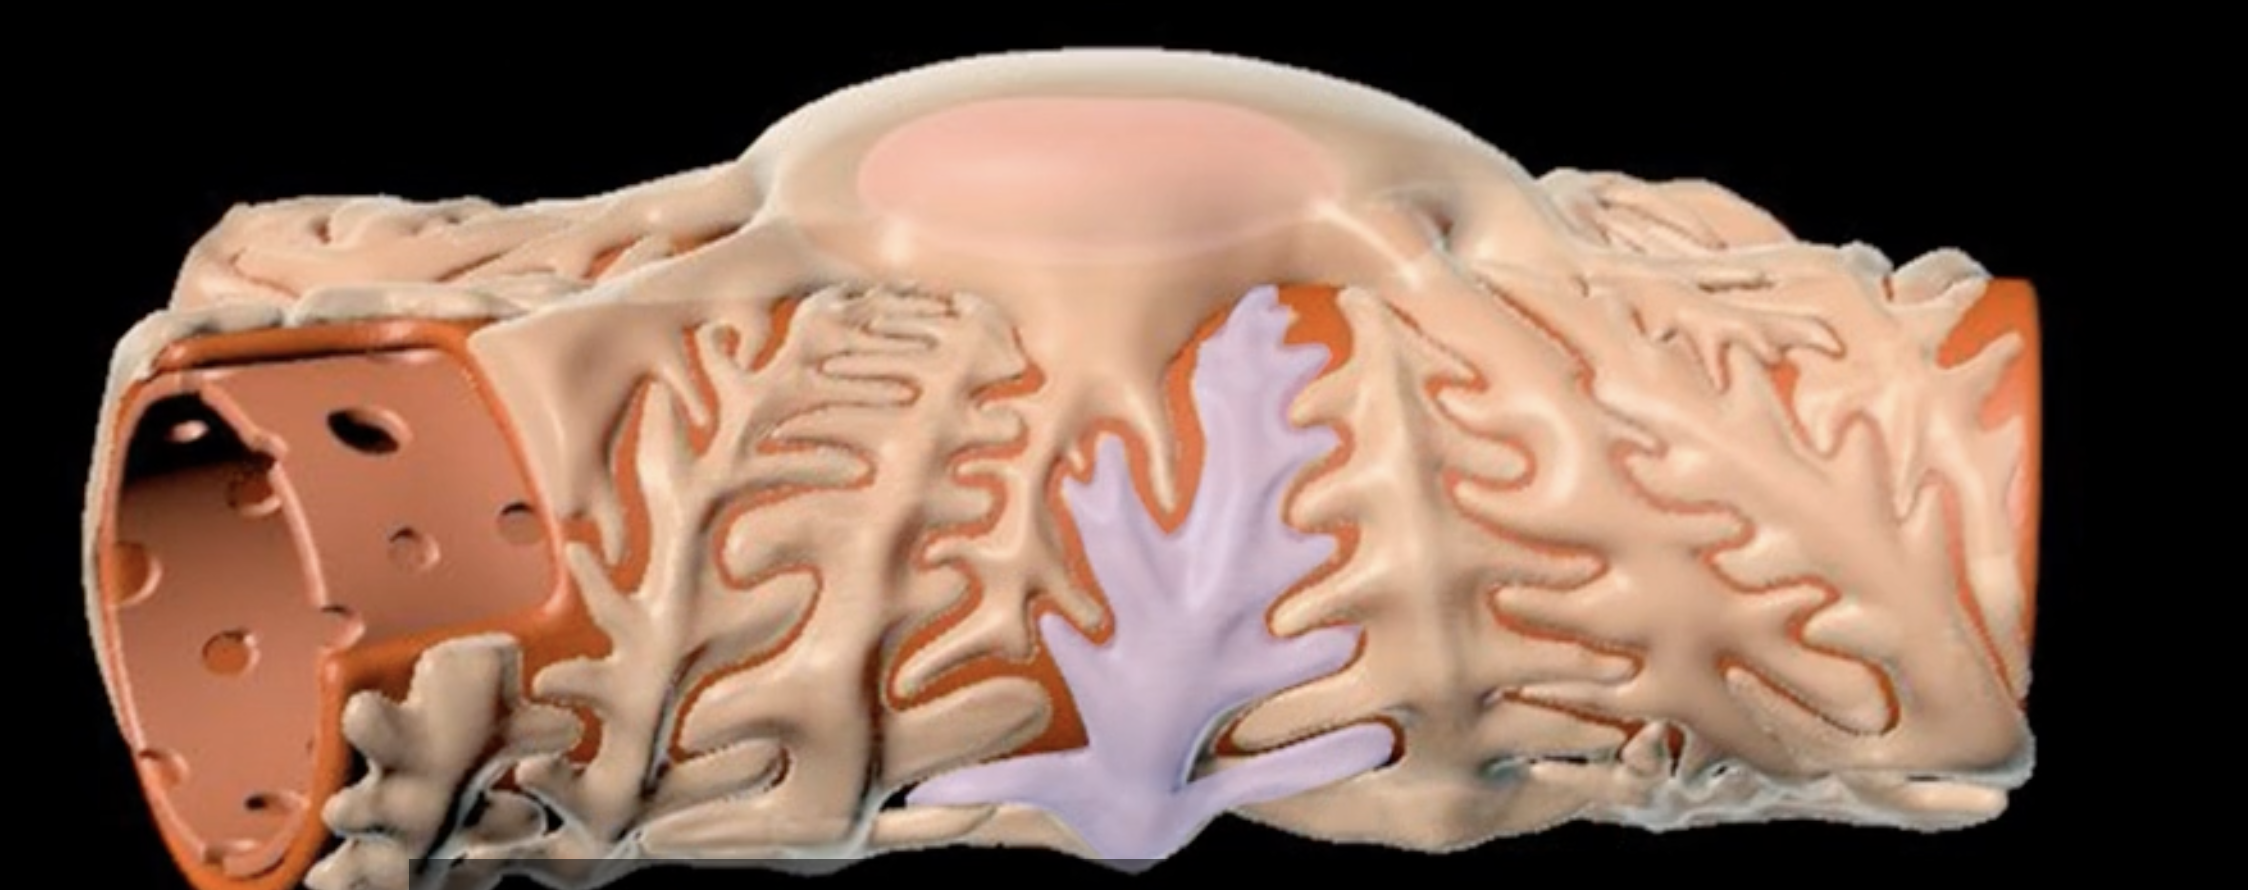

loop of Henle

red: descending limb

blue: ascending limb

red:

blue:

reabsorb ions

blue’s function

reabsorb water

red’s function

green: thick segment lined with simple cuboidal

purple: thin segment lined with simple squamous

green:

purple: